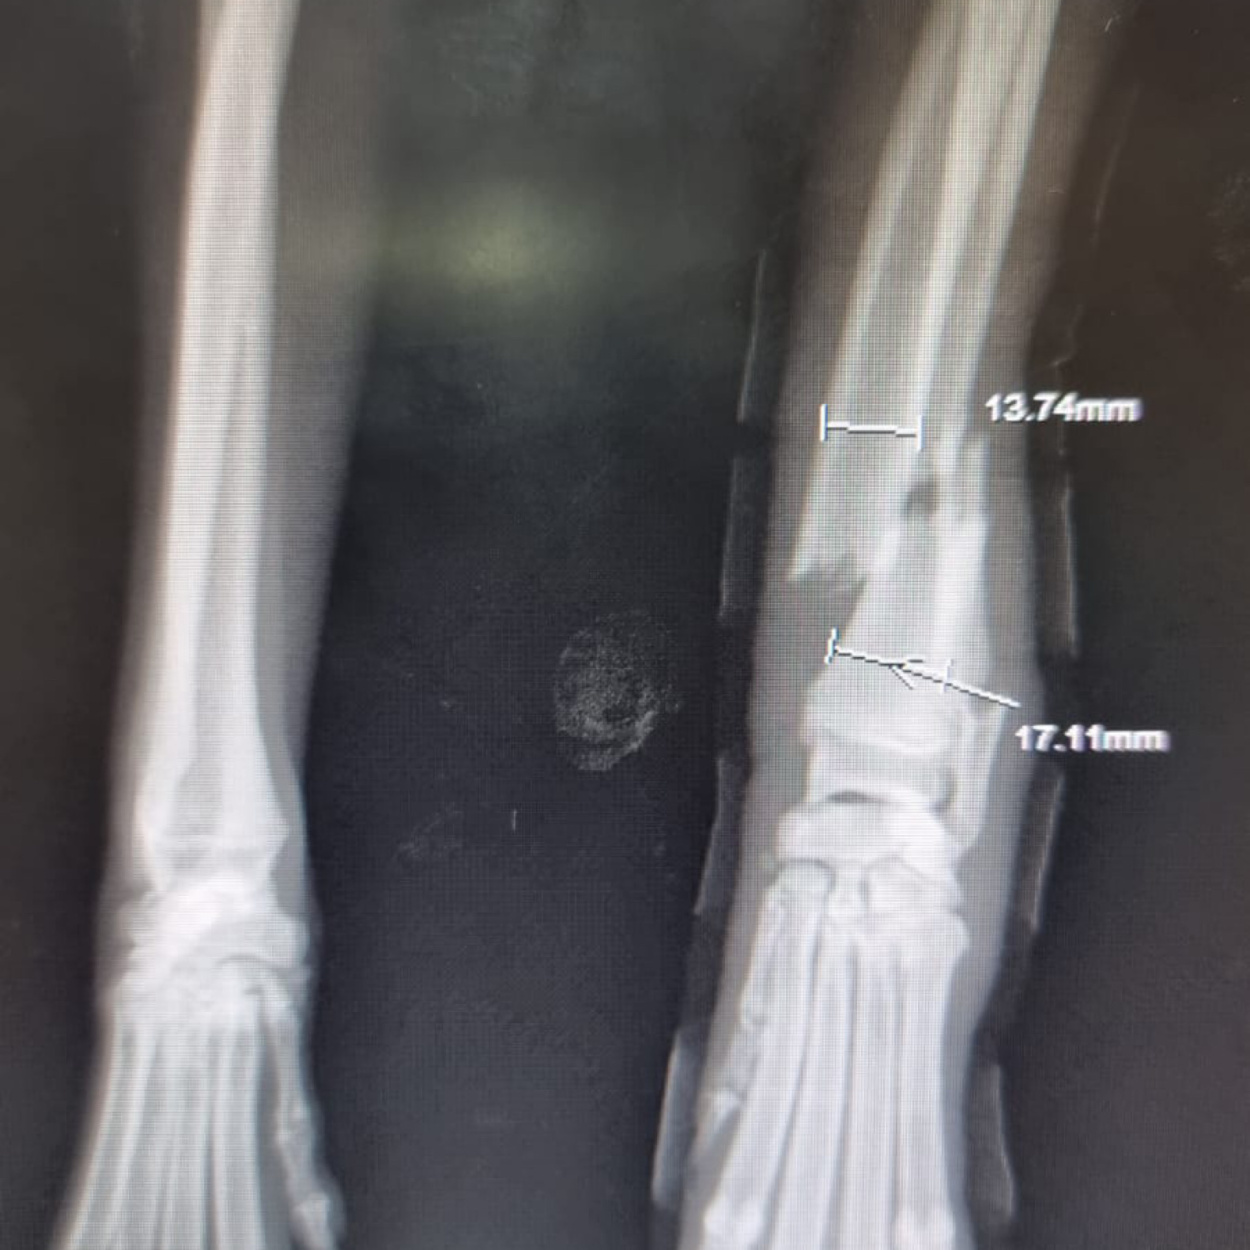

Hope konnte geröntgt werden. Was man nun sieht, tut einem schon vom hinsehen weh...

Das Gute: mit den Bildern wissen wir nun, was genau los ist und dementsprechend, was zu tun ist.